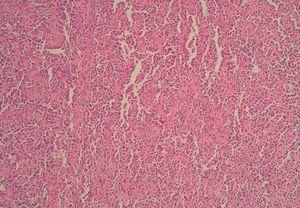

Figura 3. Inmunohistoquimia: CD31 positivo.

En la histopatología hay proliferación de células endoteliales atípicas con proyecciones papilares hacia la luz, que forman canales vasculares irregulares con tendencia a anastomosarse, tapizados por una o varias capas de células. Las células tumorales infiltran disecando fibras de colágeno y tejido adiposo. Los cuerpos de Weibel Palade están ausentes y los marcadores CD31, CD34, antígeno relacionado con el factor VIII y Ulex europaeus aglutinina son positivos4.